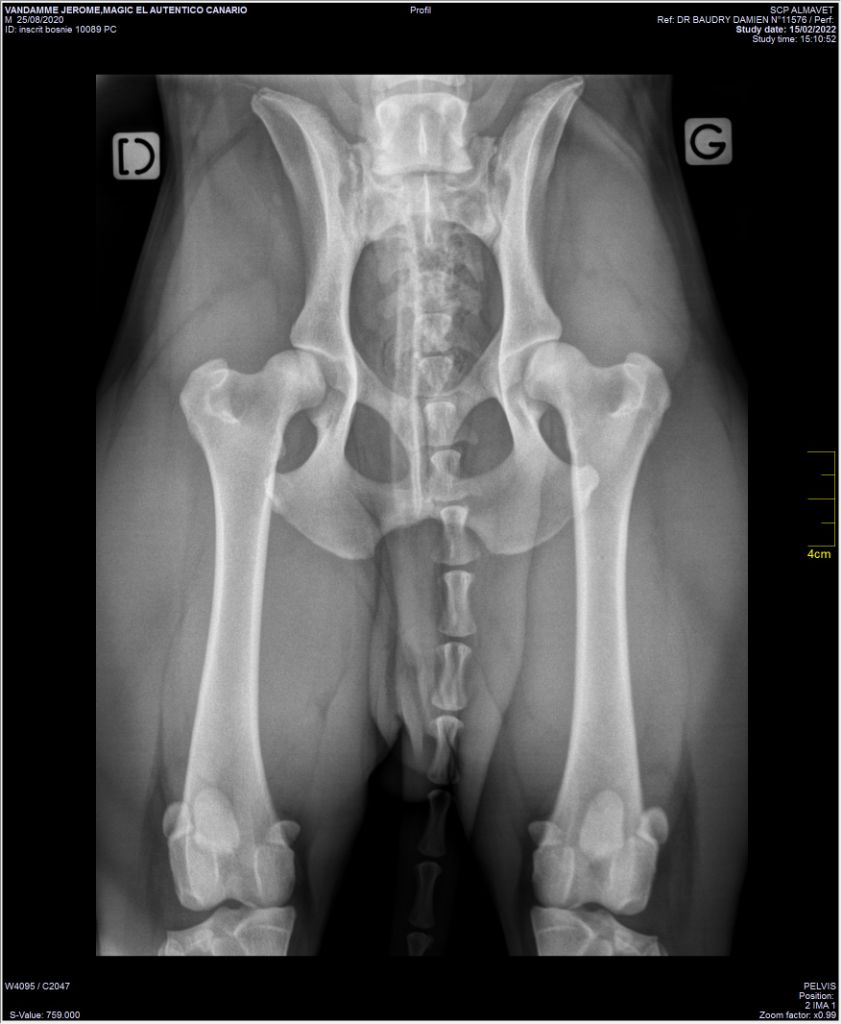

Radio des hanches de Magic

Radiographier des hanches : Lu part mon veto la lettre A/B |